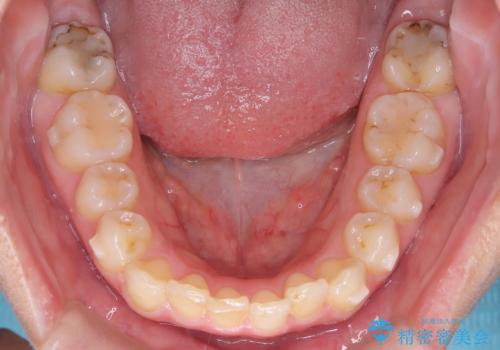

矯正後の後戻り インビザラインで改善

- 前歯のガタツキが気になると来院されました。

マウスピース矯正治療を選択しました。